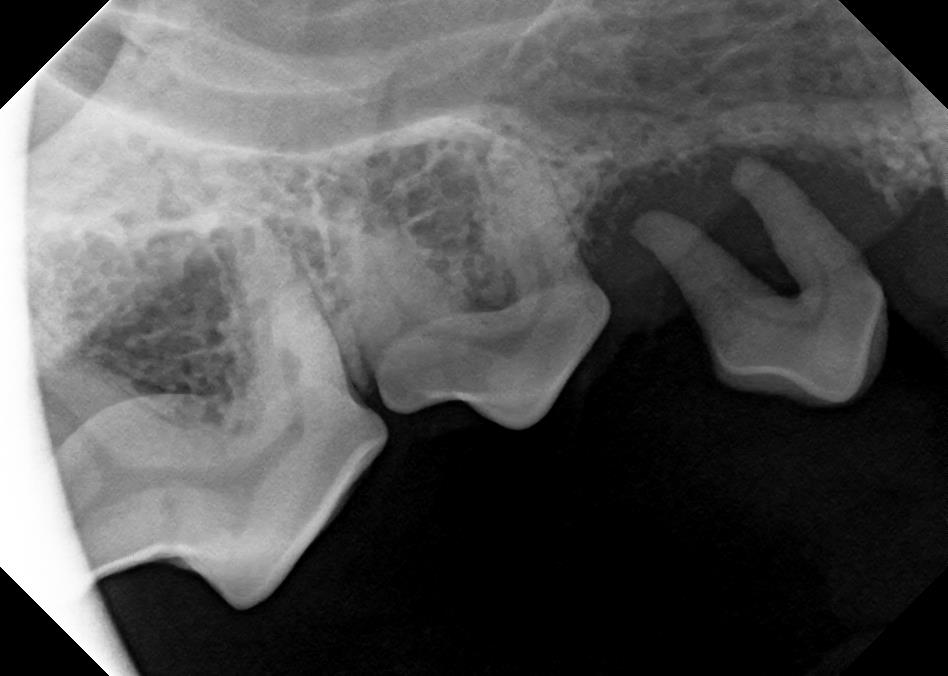

Dental X-Rays

Click on an image to learn more!